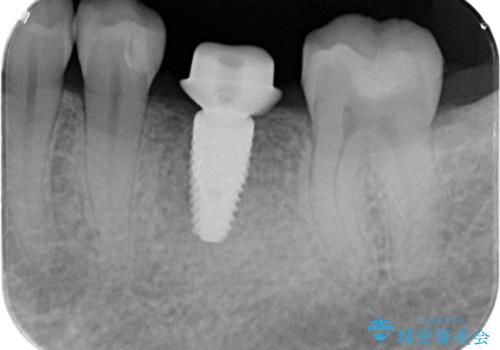

欠損部のインプラント補綴

- 失った奥歯にインプラント治療を受けたい、と希望され来院されました。

前後の歯を削らずに機能回復できるインプラントを用いて審美生、咬合機能の回復を計画します。

- 44万円(インプラント・チタンカスタムアバットメント・ジルコニアクラウン・仮歯)費用は治療当時の料金となります

痛みや腫れもほとんどなくインプラント治療を終えられ、しっかり噛むことができるようになった。と治療結果に満足いただくことができました。